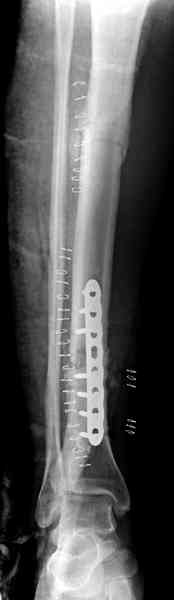

Недавно на нашей ежемесячной Morbidity&Mortality

conference мы разбирали похожий случай, ложный сустав большеберцовой кости после резекции опухоли.

Оперирован в военном госпитале с заменой сегмента

аллокостью большеберцовой кости и после демобилизации явился для постоянного наблюдения по месту жительства.

Наши имели проблему со сращением, пришлось им сделать динамизацию, дополнительную аутопластику.

Снимки представлены.